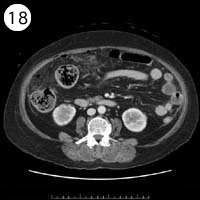

57歳 女性

単純CT

造影CT